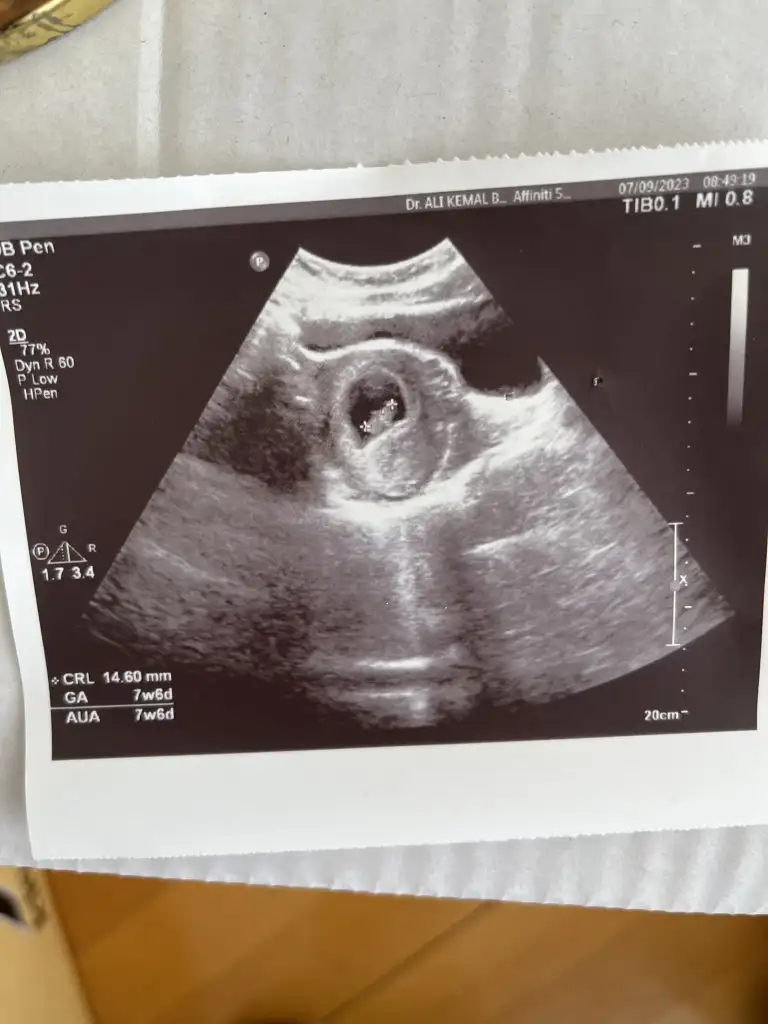

Kizlarrr sizce benim minik ne olacak 🥲

Eklentiler

• IMG_6565.webp

IMG_6565.webp

45 KB · Görüntüleme: 45